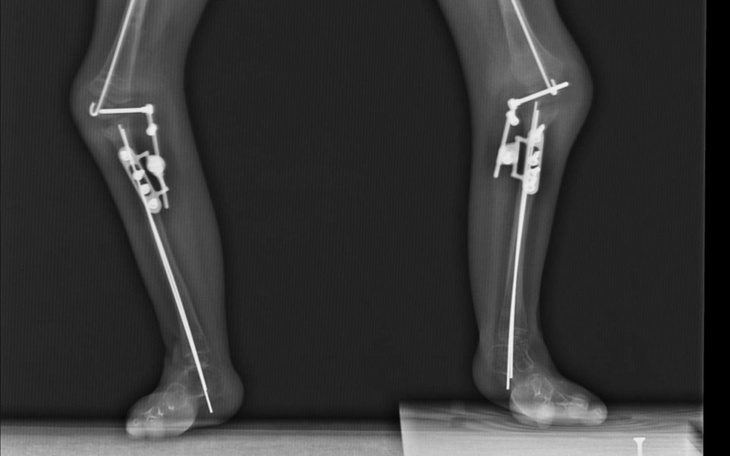

Amelia ma zaplanowaną operację w grudniu w Paley European Institute w Warszawie,którą przeprowadzi dr Paley. Koszty są bardzo duże i niestety poza naszym zasięgiem. Potrzebujemy w miesiąc uzbierać 37 000 zł.

Operacja jest konieczna aby nie zaprzepaścić dotychczasowych efektów i nie zachamowywac wzrostu nóg.

Przeszłam 3 skomplikowane operacje w Paley Institute na Florydzie. Po prawie 9 miesiącach nieustannego bólu oraz walki zakończyłam leczenie i wróciłam do domku...chodzę teraz na własnych nóżkach. To cud,który dokonał się dzięki Waszej pomocy. ❤